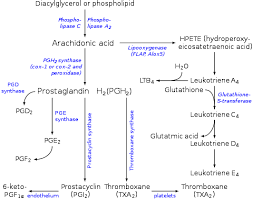

قیمت: 32٬000 تومان - دسته بندی فایل: پاورپوینتپاورپوینت پروستاگلاندین ها

فروش ویژه پاوزپوینت حرفه ای پروستاگلاندین ها با تخفیف استثنایی قیمت 49 تومان تعداد اسلاید: 15 اسلاید